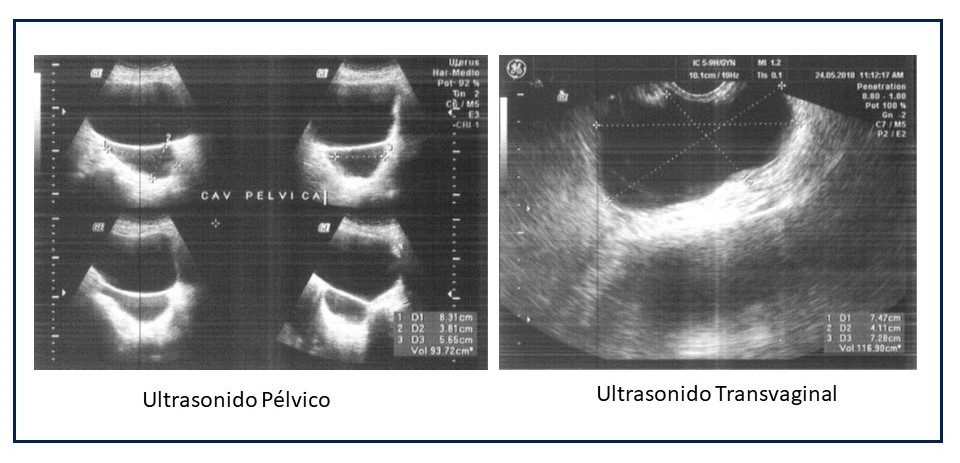

Soy fiel defensora de la medicina preventiva y trato de vivir lo que predico, por lo que acudí a mi control ginecológico anual, dentro de la consulta me realizan un ultrasonido transvaginal para evaluar mis ovarios, ya que no tengo útero por histerectomía previa indicada por hemorragias, en este estudio se observa un quiste ovárico de gran tamaño. Mi médico me remite a un especialista en imágenes quien repite el estudio, esta vez con doppler, confirmando el diagnóstico de tumor quístico de ovario derecho con un diámetro alrededor de 8 cms.